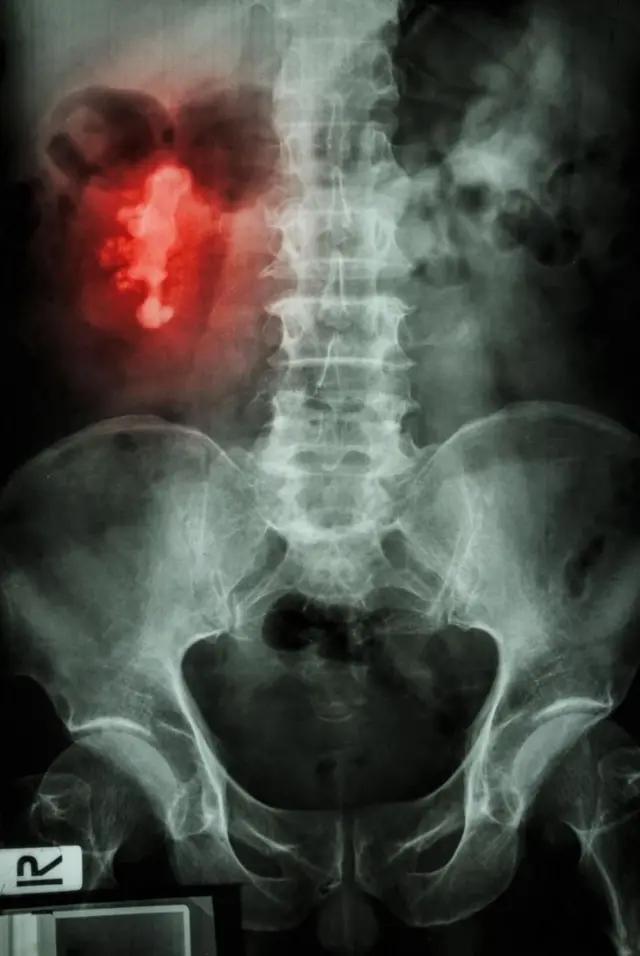

Mawe kwenye figo huathiri takribani mtu mmoja kati ya kumi. Huibuka hasa kutokana na kemikali ya kalsiamu na chumvi, ambayo huvuja kutoka kwenye damu hadi kwenye mkojo.

Mawe ya figo yanaweza kutofautiana ukubwa, kutoka ukubwa wa chini ya milimita kwa upana hadi sentimita au zaidi. Yanaweza pia kuwa na maumbo tofauti tofauti.

Mawe haya husababisha matatizo yanapoziba mirija ya ureta, mirija miwili inayosafirisha mkojo kutoka kwenye figo hadi kwenye kibofu. Ikiwa hilo litatokea, linaweza kusababisha maumivu makali chini ya mgongo, pamoja na kuzuia mtiririko wa kawaida wa mkojo. Na kusababisha maambukizi au mkusanyiko wa mkojo ndani na karibu na figo.